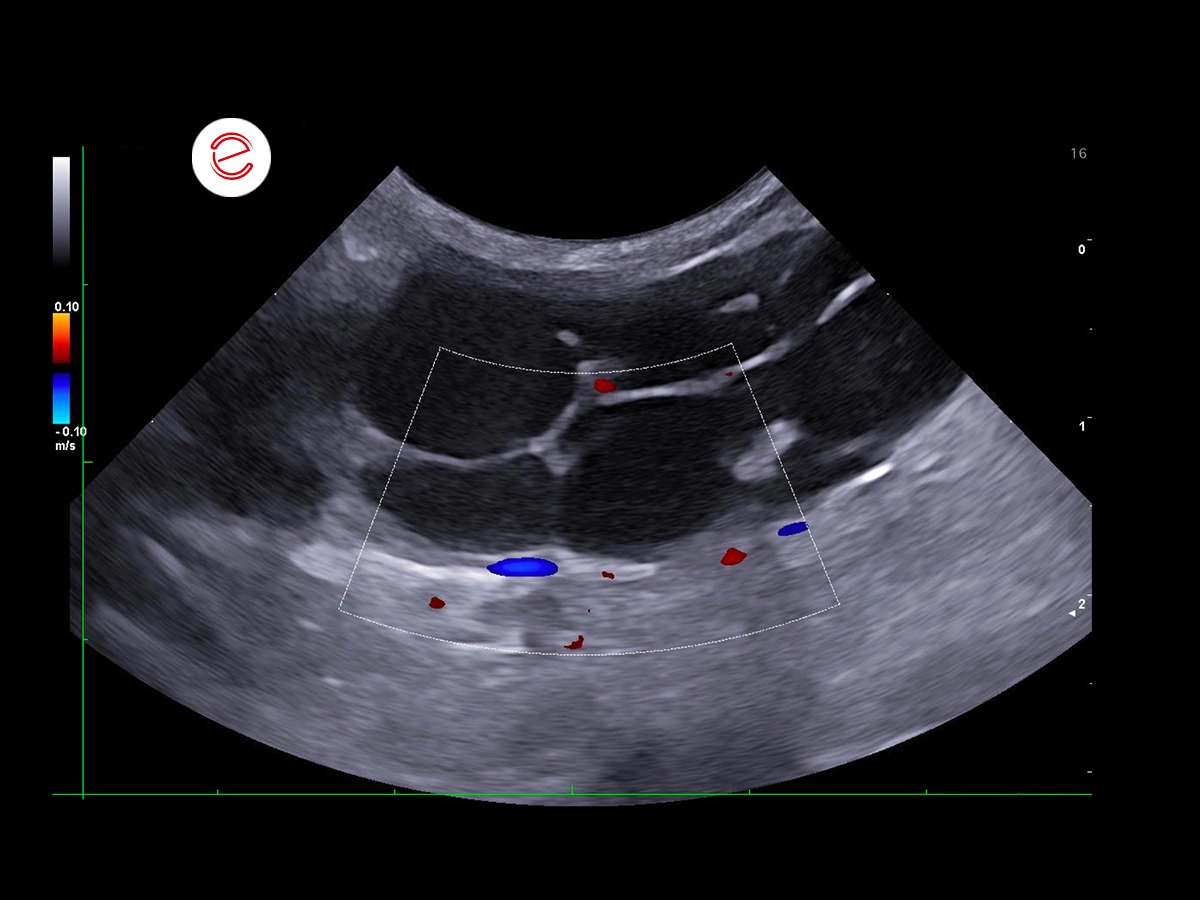

A multilobulated subcutaneous lesion consisting of multiple anechoic cavities with thin hyperechoic walls was observed in the right inguinal region, measuring up to 1.5 cm in diameter, and extending within the subcutaneous tissue in a cranio-caudal direction for approximately 7 cm.

Doppler interrogation showed minimal peripheral vascularization.